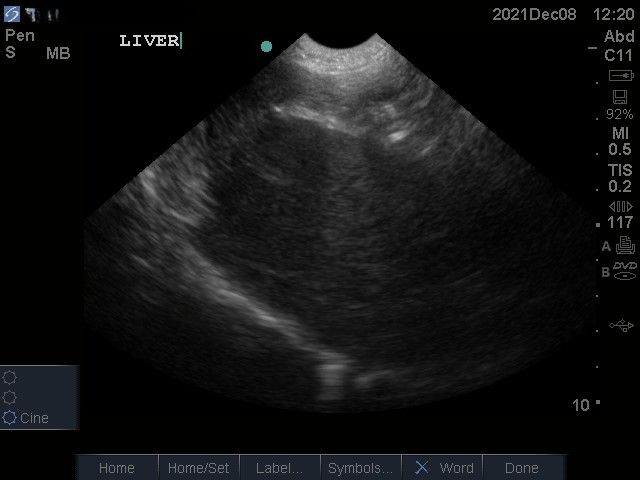

I have used the C11x probe (5-8MHz) which has been good for abdominal scanning of cats, small dogs and basic echocardiography. The depth obtainable (13cm) on the probe I have used is disappointing for large dogs. Having said that the image quality is reasonable. I have not been able to source new prices for this machine (if you are selling them please do get in touch!), however one machine I saw being sold second hand was well under £10,000 which suggests it’s starting price is <£10,000.

Images from the M Turbo